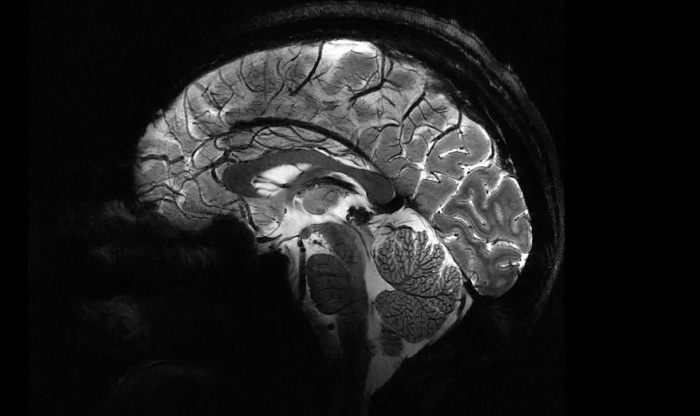

Главным отличием Iseult является возможность сканирования мозга в намного более высоком разрешении. Всего за 240 секунд он способен сделать снимки человеческого мозга в виде 1-миллиметровых срезов. Обычный МРТ для получения таких результатов потребует 2 часов неподвижного нахождения пациента внутри.

Несколькими годами ранее Iseult испытывался на тыквах, сейчас его протестировали на 20 добровольцах. Полученные изображения раскрывают весь потенциал технологии МРТ и позволяют лучше понять, как работает мозг. При этом, сверхмощный томограф может быть полезен не только ученым, но и медикам. С его помощью можно изучать и диагностировать такие нейродегенеративные недуги, как болезни Паркинсона и Альцгеймера.